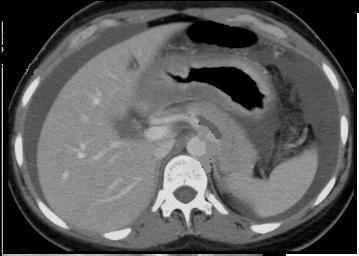

Adeno carcinoma

de l'estoma , forme linite plastica avec

epaississement maruee de la paroi gastriue ( image

TDM en coupe axiale |

|

Meme cas en coupe coronale (frontale

) |